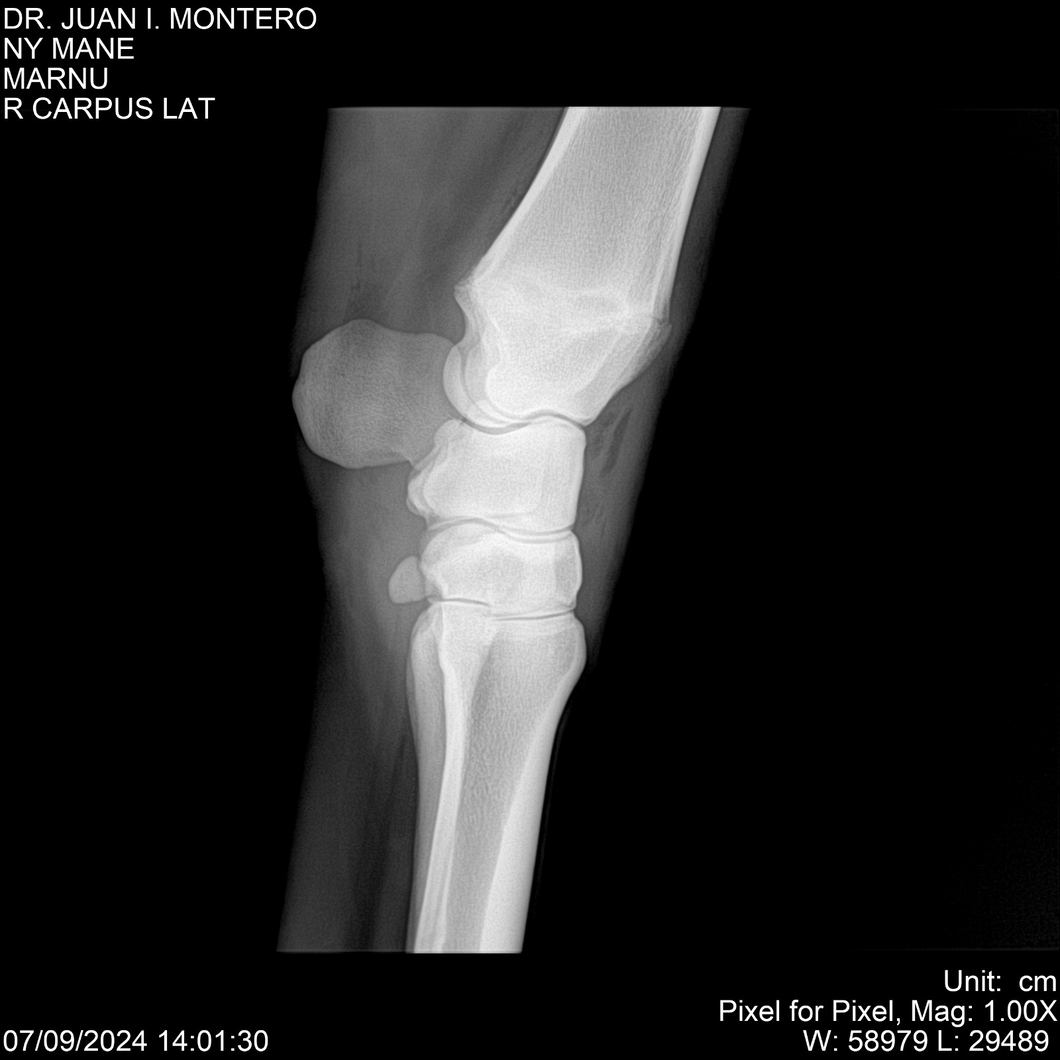

LOTE 20, NY MANE Lote Anterior Volver al remate Lote Siguiente Ficha Contacto Montevideo - Ficha del Lote Identificador: #282520 Categoría: Yeguarizos 76 Visualizaciones ClicData Contacto Empresa: Abelenda N. R., Walter Hugo Nombre*: Teléfono* : E-mail* : Mensaje Enviar Registrese gratis Este contenido Exclusivo está disponible sólo para usuarios registrados Ingresar